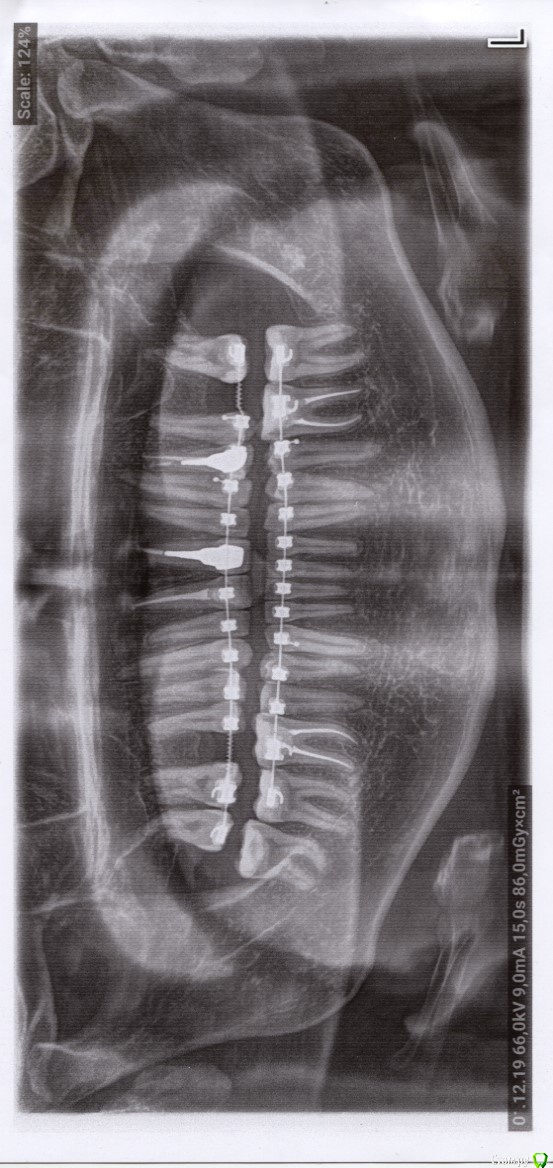

Больше года ношу брекеты, недавно была имплантация, а значит при удачном раскладе весной будет снятие брекетов и протезирование.

Почти год допекает 11-й зуб. Прошлой осенью пролечили глубокий кариес и сделали реставрацию, затем зуб начал ныть и в феврале этого года его депульпировали. Зуб успокаивался очень долго, месяцев 5, если не больше. Беспокоила именно боль при постукивании/надавливании, сам по себе зуб никогда больше не болел. На вертикальное надавливание реакции нет, а вот при горизонтальное, когда как бы раскачиваешь зуб на или от себя, реакция есть. Достаточно даже просто задеть губой брекет на этом зубе. Флосс между 11 и 12 протискивается с теми же неприятными ощущениями. После очередных активаций у ортодонта зуб первую неделю при прикосновении болит пуще прежнего, а затем опять успокаивается до текущего уровня.

Ни один терапевт при просмотре КТ и снимков ничего не находил, кроме материала за верхушкой. Никакого смысла перелечивать не видят. Чувствительность чаще всего списывают на нагрузку от брекетов, но за последний месяц я дважды оставался без дуги и никаких изменений в чувствительности нет.

Прикрепляю срез. Видно материал на верхушке. Но болезненная перкуссия в таких случаях вроде как при вертикальных нагрузках, а не горизонтальных.